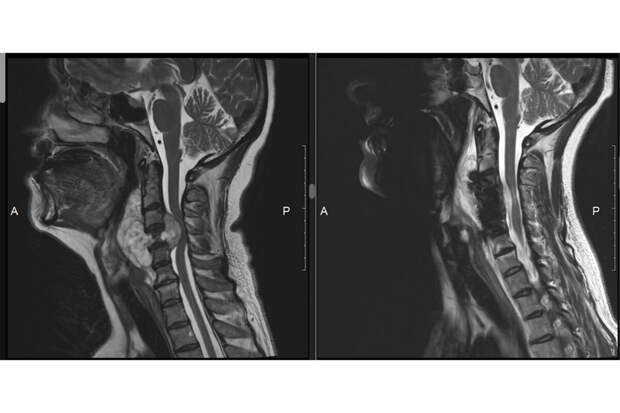

Во время обследования у женщины обнаружили большую опухоль в шейном отделе позвоночника, которая разрушила один из шейных позвонков и сдавила спинной мозг.

Женщине оперативно провели операцию. Специалисты удалили опухоль и стабилизировали работу позвоночника. Так как один из позвонков был разрушен, на его место установили имплантат.